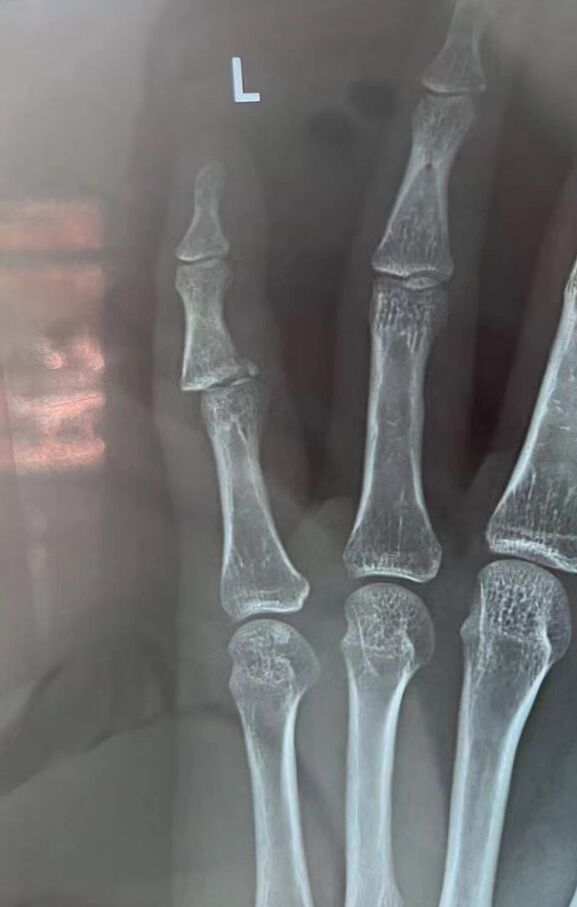

手术设计

微信图片_20240319205700.jpg